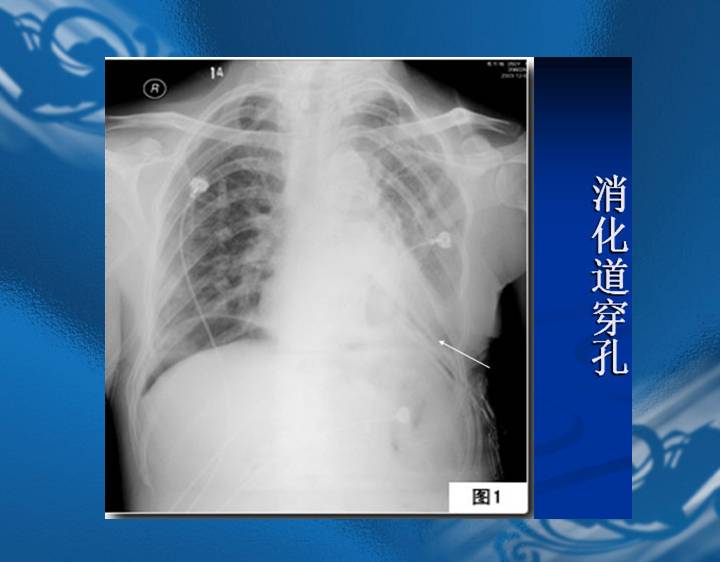

执业医师资格考试“实践技能”影像学辅导资料